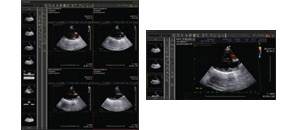

EMR Embedded PACS

- The first embedment in the electronic chart of veterinary clinics in the world

- Composition of one perfect system by combining EMR with PACS

- Innovative integral system getting out of the simple connection

from the existing PACS and electronic chart - Possible to confirm the previous PACS image in the IntoVetGE

- Easy image inquiry through the Work List in the IntoVetGE Today